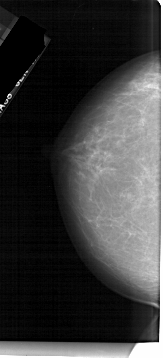

A_1694_1.RIGHT_MLO

RIGHT_CC LINES 5146 PIXELS_PER_LINE 2296 BITS_PER_PIXEL 12 RESOLUTION 43.5 NON_OVERLAY